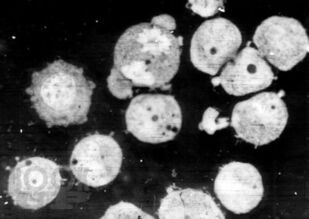

Книга посвящена описанию животных моделей in vivo для отбора, углубленного и/или доклинического изучения цитостатиков, а также некоторых таргетных средств. Представлены основные биологические характеристики, дополненные лекарственной чувствительностью и востребованностью в настоящее время.

Информационный материал предназначен для исследователей, работа которых связана с поиском, углубленным или доклиническим изучением in vivo новых противоопухолевых агентов.